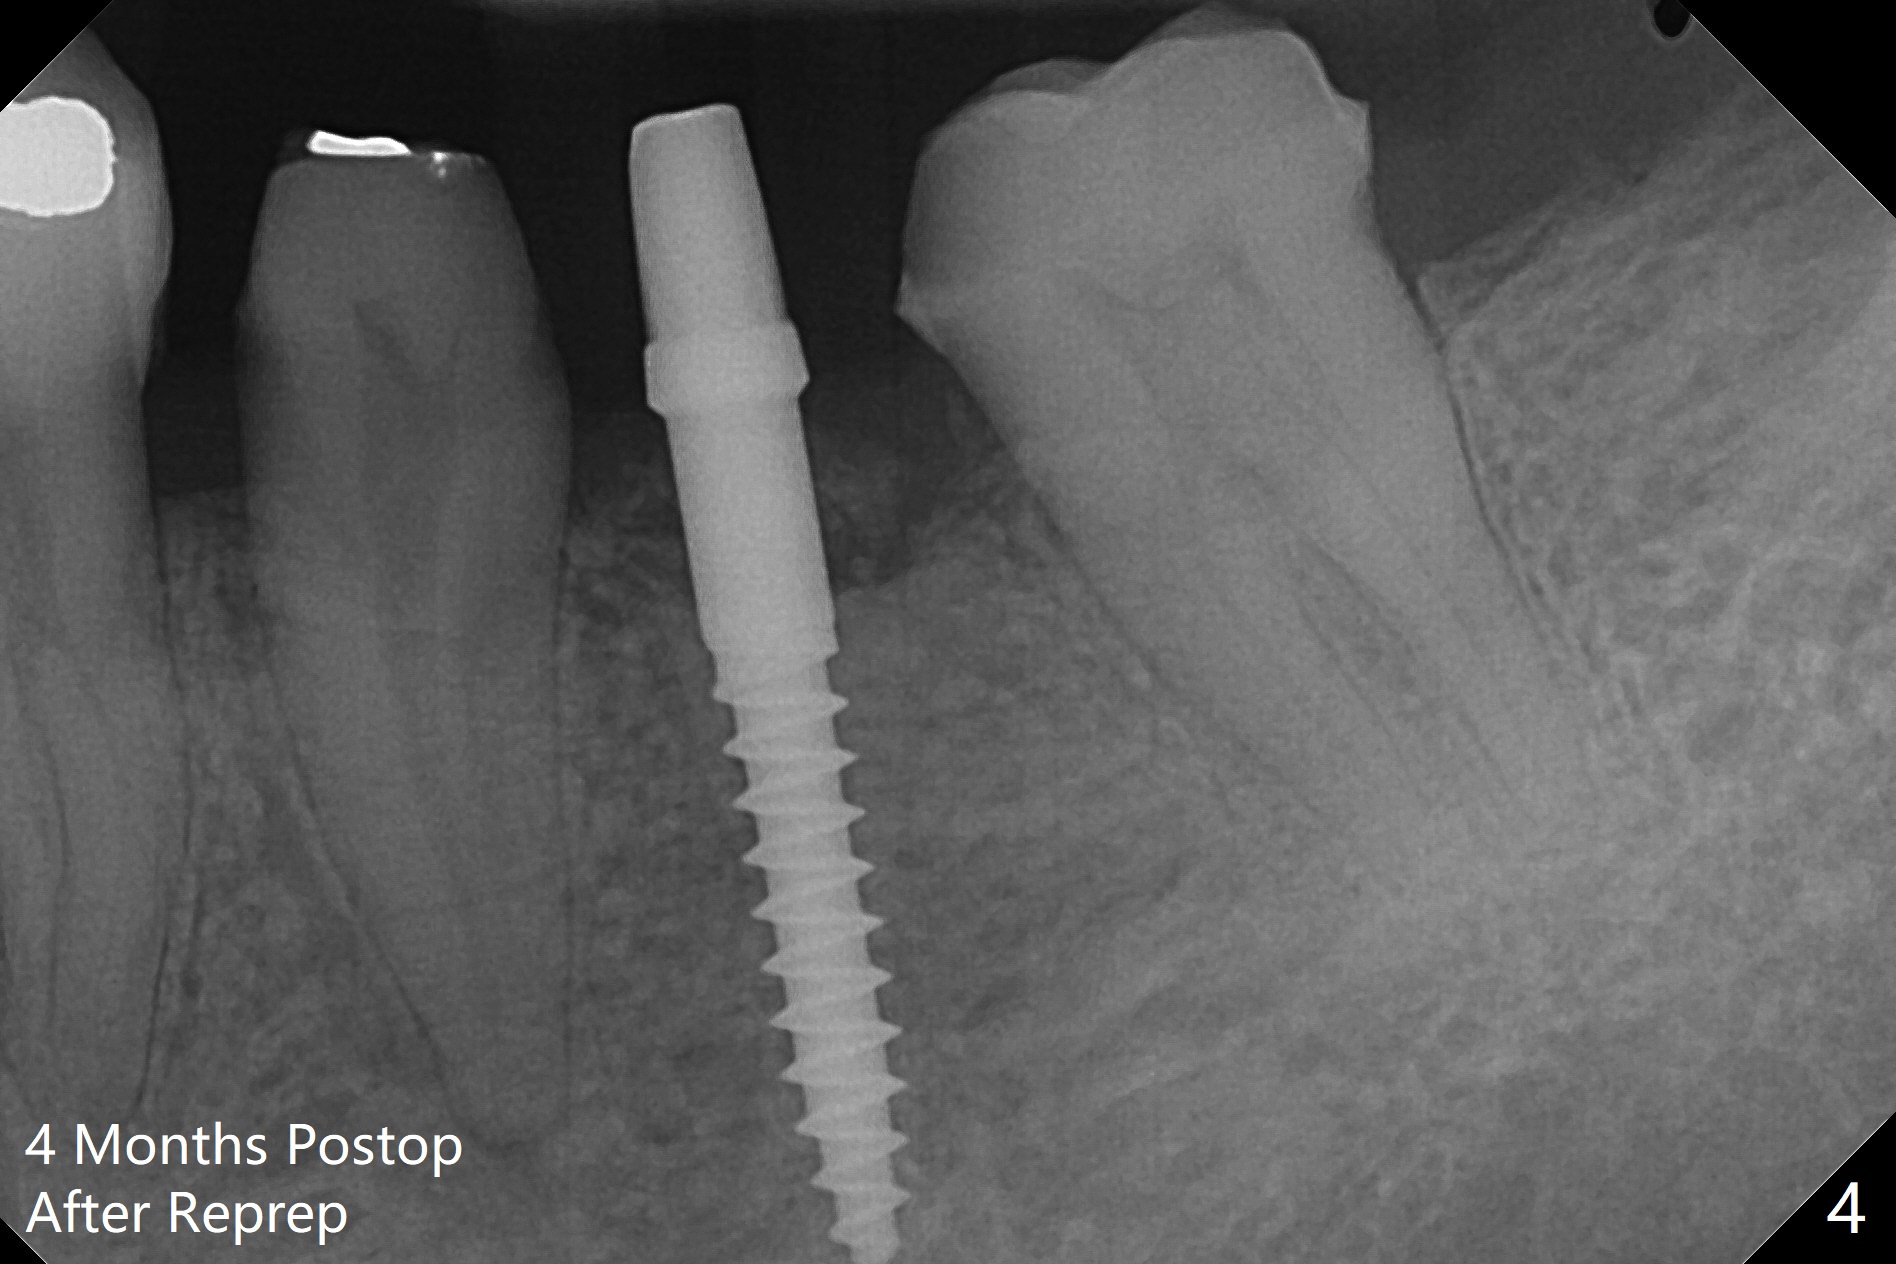

To start osteotomy in the narrow ridge with the oblique top, the latter needs to be trimmed at #19. It would be less traumatic to have a narrow bone trimmer (e.g., 3 mm) in the Narrow Guide Kit. This case is originally designed to have ridge split. The ridge top is trimmed with surgical handpiece after incision. Following pointed drill, the cylindrical part of the 2.2x8.5 mm drill cannot engage to the metal sleeve with 10.5 mm offset. The guide has to be removed. The first 1-2 mm osteotomy has to be done free hand before reuse of the guide and the drill. Nevertheless, the osteotomy is precise buccolingual when it is finished (Fig.1). If the short drill (2.2x7.3 mm) cannot be produced, the next case should have 12 mm offset for narrow guide and an additional guide with regular metal sleeve for tissue punch and bone trimmer. Since the mesiodistal space is also limited, a 2.5x12(4) mm 1-piece implant is placed instead (Fig.2). With the implant placed a little deeper (Fig.3 arrow), bone graft is placed (*), followed by suture. When the procedure is done, the patient is tired. It would be nice to have a more complete Narrow Guide Kit with its own bone trimmer and 2.2x7.3 mm drill. There is no bone loss with retention of bone graft 4 months postop; after reprep of the neighboring teeth, impression is taken (Fig.4). The three crowns are cemented 4.5 months postop (Fig.5).